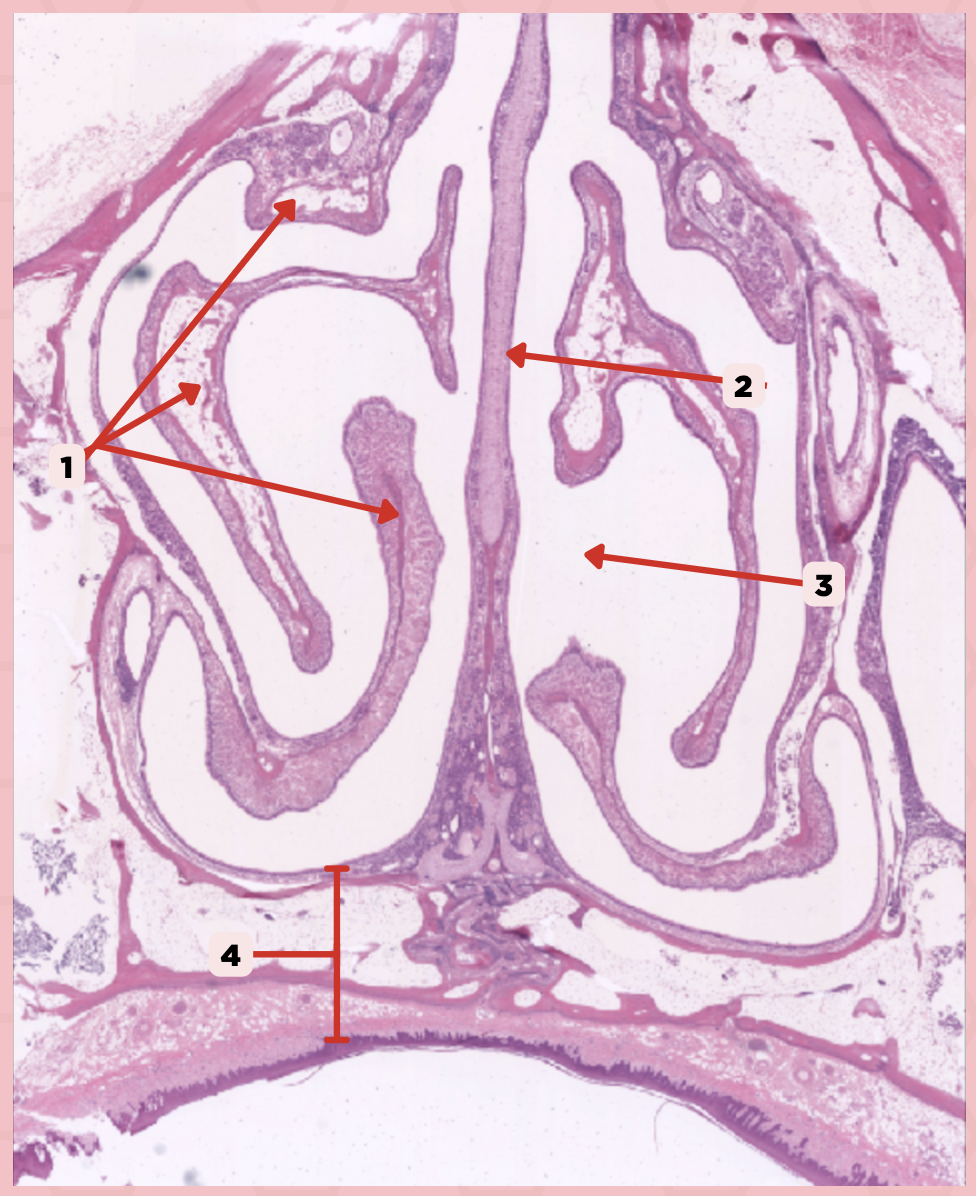

Nasal Cavity

What are the spaces found immediately lateral to #2?

Nasal Turbinates (conchae)

Identify the structure labeled as 1.

Nasal septum

Identify the structure labeled as 2.

Nasal cavity

Identify the structure labeled as 3.

Hard palate

Identify the structure labeled as 4.

Mucosal Associated Lymphoid Tissue (MALT)

What time of lymphocyte is numerous in the nasal cavity?